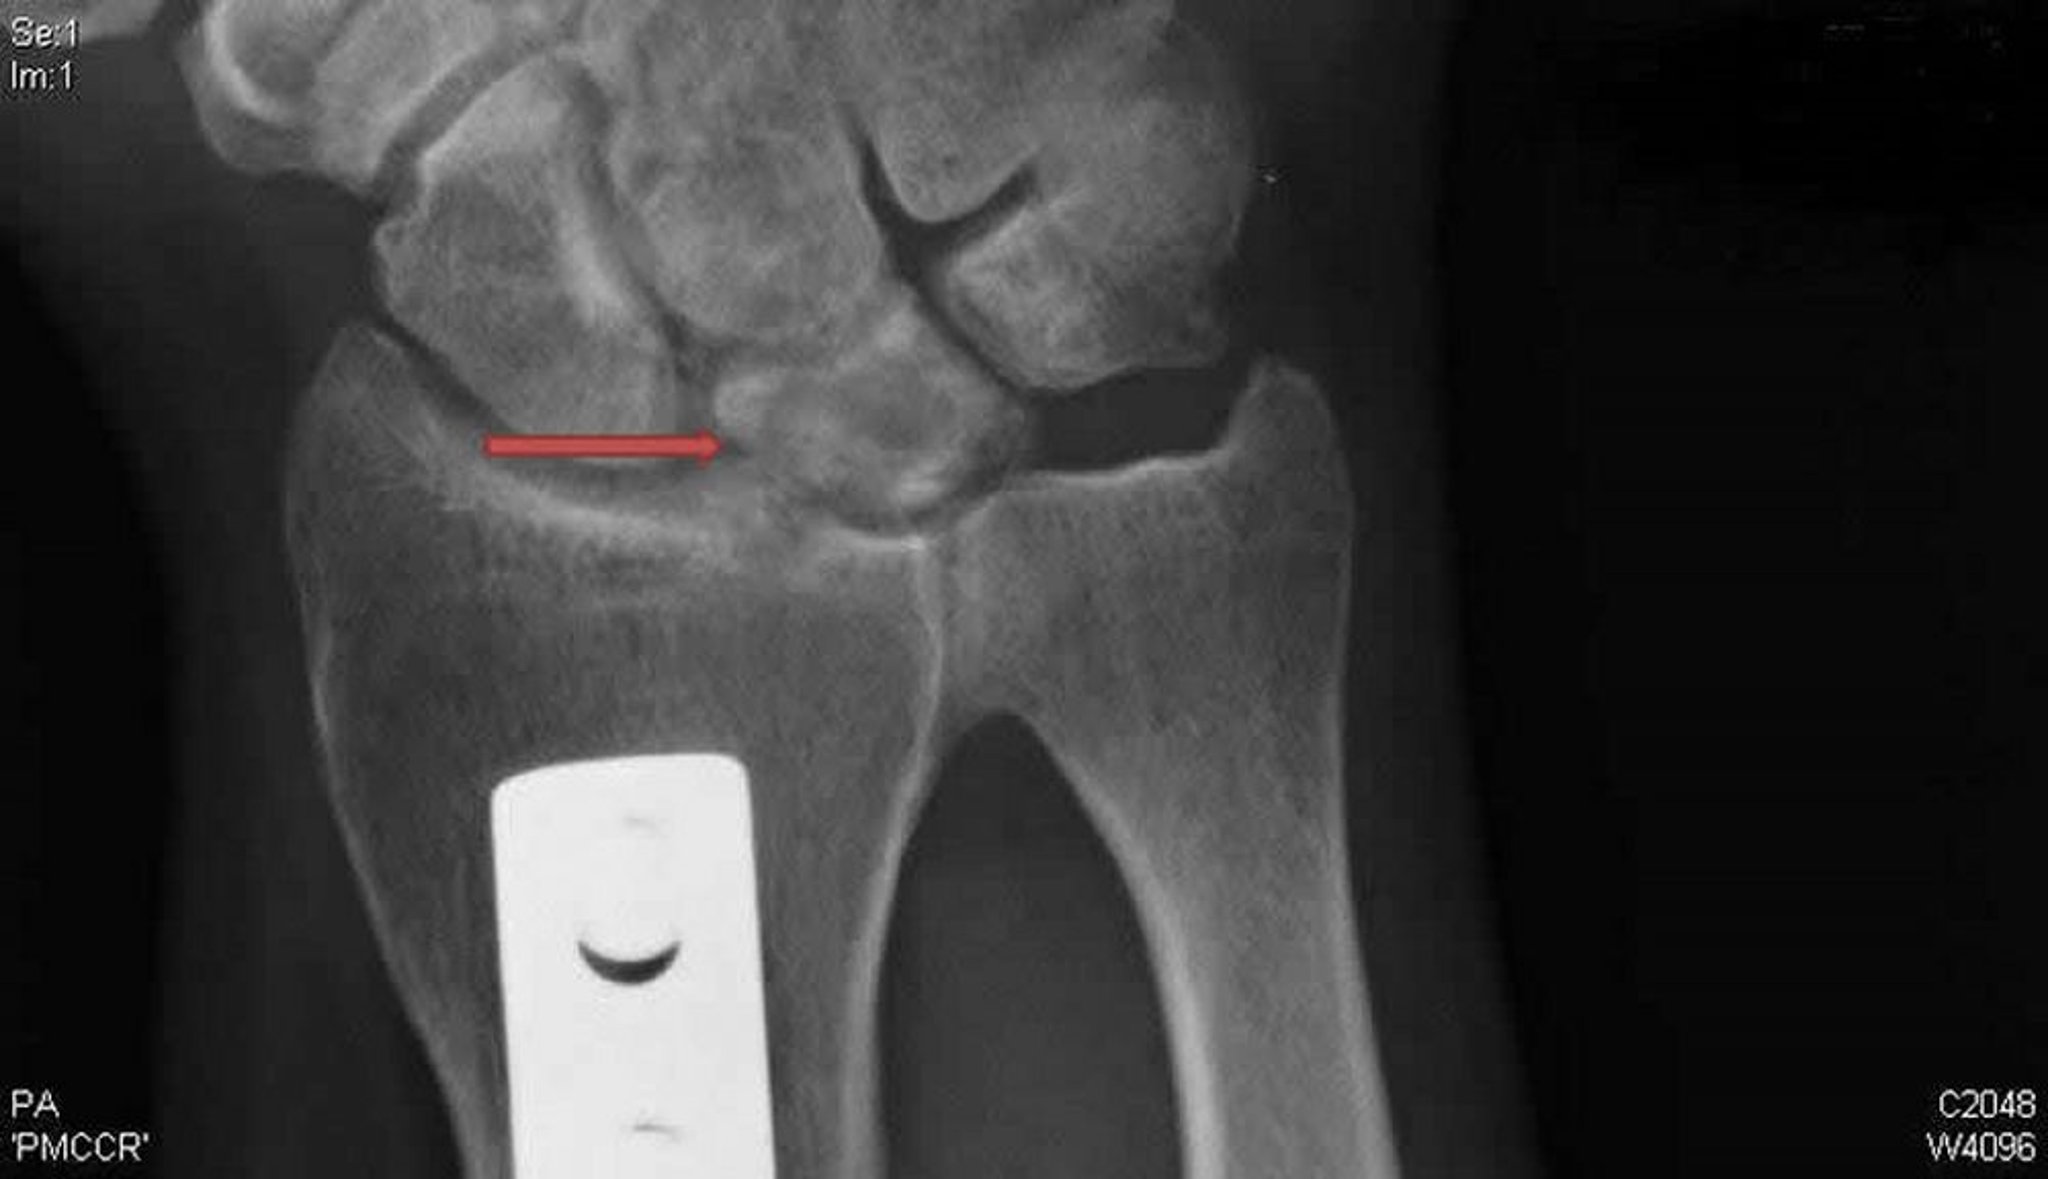

Để chẩn đoán bệnh Kienböck, chụp MRI và chụp CT là nhạy nhất; X-quang cho thấy những bất thường muộn hơn, thường bắt đầu bằng xơ cứng xương nguyệt, sau đó là các nang thay đổi, phân mảnh và xẹp.

Phim chụp X-quang do bác sĩ David R. Steinberg cung cấp